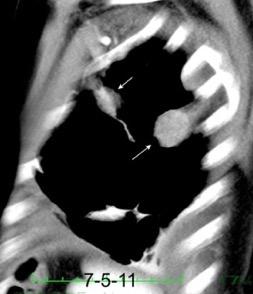

Signo de la Pleura separada “Split pleural sign”

Capas pleurales de grosor uniforme realzadas por el contraste

No específico de empiema. Indica “exudado”. 68% de pacientes con empiema pleural.

Capas pleurales de grosor uniforme

Realce grasa extrapleural (30%)

> Grasa Extrapleural. (60-80%)

Kraus GJ. Split pleural sign. Radiology 2007